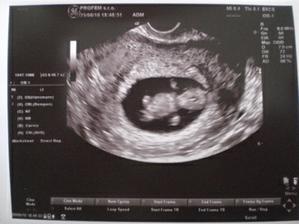

Ultrazvuky a bruska

krasne 4D fotky 🙂